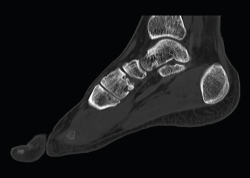

Figura 3. Imagen radiológica sagital donde se objetiva la consolidación en buena posición de la artrodesis.